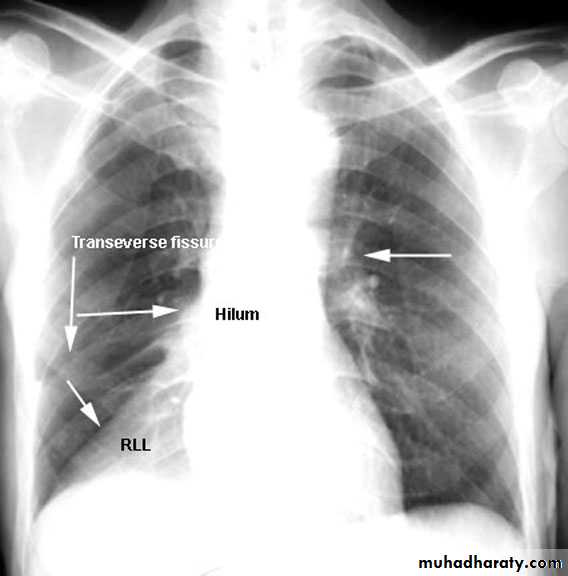

Lung Anatomy

Zonal anatomyLobar anatomy

Rt lung divided to 3 lobes (upper , middle & lower )

Transverse fissure separate the upper lobe from middle lobeOblique fissure separates the upper & middle from lower lobe .

The left lung subdivided to two lobes by oblique fissure ( upper & lower )

Rt upper lobe

Rt middle lobe

Rt lower lobe

Left upper lobe

LUL collapse

Left lingula

Left lower lobe